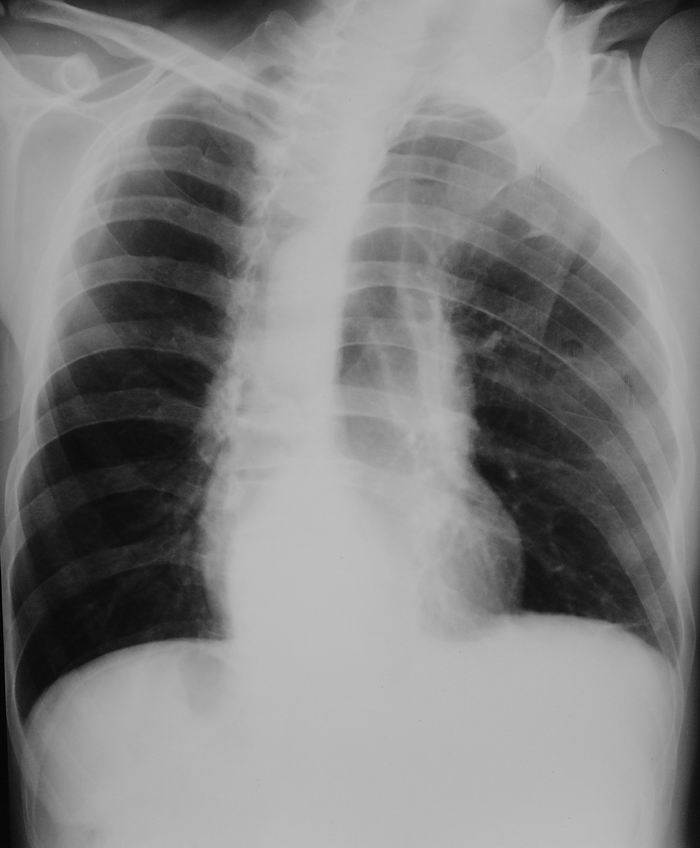

男性,47岁,车祸致胸痛2小时。

请大家看看后纵隔食道及降主动脉周围的软组织密度灶是什么?双侧膈肌脚内侧及椎管内的气体影是怎么回事?

伤者今天上午又来照了胸正斜位、立腹片、腰椎片: